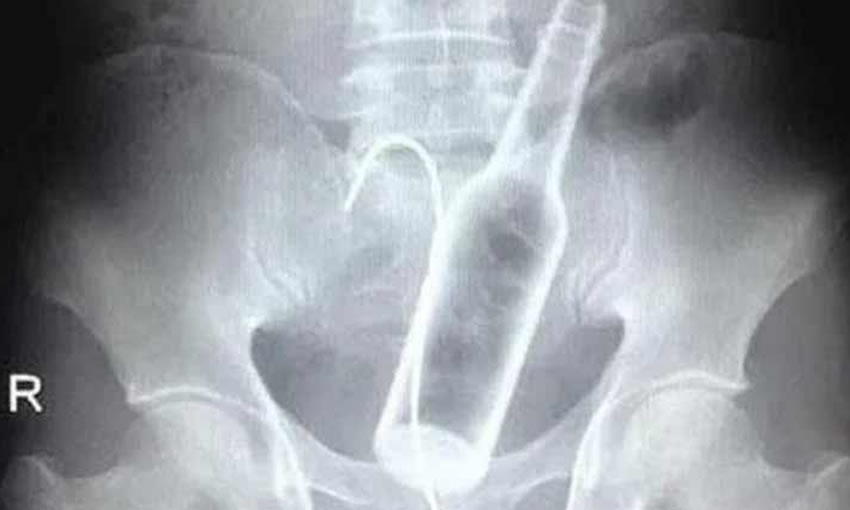

O homem chegou ao hospital reclamando de fortes dores abdominais

Através de exame de raio X foi confirmada a denúncia

Após avaliação clínica, o rapaz foi submetido a uma cirurgia para remoção da garrafa.